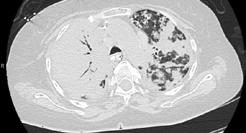

CASE PRESENTATION

A 58-year-old female with recently diagnosed COVID-19 pneumonia was found to have a dry cough and dyspnoea in the setting of persistent bilateral hilar and mediastinal lymphadenopathy associated with bilateral nodular infiltrates. Of note, she immigrated to the USA from India 10 years prior, with the most recent travel to India 2 years ago. Quantiferon testing upon return to the USA was negative at that time. Workup included bronchoscopy with endobronchial ultrasound revealing non-caseating granulomas with negative stains for acid-fast bacilli (AFB). She was diagnosed with Stage 3 sarcoidosis and initiated on prolonged steroid taper with improvement of symptoms. With taper of steroid dose, however, she developed lymphocyte-predominant exudative effusion with negative cultures, and was reinitiated on a protracted steroid course with rapid symptom resolution. At 4-month follow-up, she had worsening CT findings upon steroid taper, and was started on azathioprine. One month later, she required hospital admission for worsening dyspnoea and fatigue. She was noted to be febrile, tachycardic, and tachypnoeic with worsening

hypoxia. Subsequent CT chest showed progression of bilateral nodular infiltrates with new right upper lobe consolidation and air bronchograms concerning for multifocal pneumonia (Figure 1). Incidentally, she was also noted to have calcified splenic granulomas. She developed rapid clinical deterioration, ultimately requiring mechanical ventilation, pressor support, and continuous renal replacement therapy. Repeat bronchoscopy revealed diffuse alveolar haemorrhage with multiple AFB smears positive for Mycobacterium tuberculosis. She was immediately initiated on quadruple therapy, but unfortunately, despite treatment, developed refractory shock and passed away 2 weeks after initial presentation.

TB and sarcoidosis share synonymous manifestations, making differentiating between progression of sarcoidosis and the development of TB difficult, especially in patients who have biopsy-proven sarcoidosis. This patient’s initial negative Quantiferon testing and AFB stains, CT scan findings, pathology, and rapid symptom resolution with steroids support the initial diagnosis of sarcoidosis. Given her history and no recent identifiable risk factors, TB was lower on the differential at initial presentation to the hospital. While findings of lymphocytepredominant pleural effusions3 and splenic granulomas may be seen with sarcoidosis, this should raise suspicion for tuberculosis

A) Initial adenopathy with peripheral patchy ground glass opacities in the right lung following COVID-19 pneumonia. B) Persistent bulky adenopathy 1 year after initial presentation. C) Extensive nodularity throughout the right lung with increasing confluent opacities in the right upper lobe and stable mediastinal lymphadenopathy 2 years after initial presentation. D) Tuberculosis superimposed on sarcoidosis with progression of nodular infiltrates, worsening right upper lobe consolidation, and air bronchograms with incidental calcified splenic granulomas (not pictured).

Figure 1: CT progression of patient’s sarcoidosis and tuberculosis.

and prompt further investigation. This case highlights diagnostic challenges and the need to keep TB on the differential in patients with previous risk factors, despite negative testing and progressive CT findings with biopsyproven sarcoidosis.